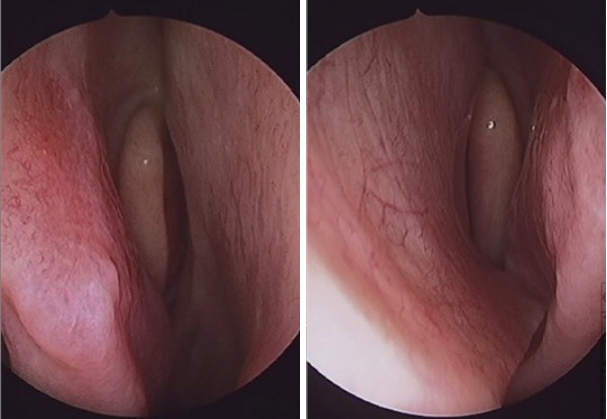

특이 병력이 없는 24세 남자 환자가 1년 전부터 발생한 우측 비폐색 및 간헐적인 수양성 비루, 후비루를 주소로 내원하였다. 비내시경 소견상 좌측으로 편향된 비중격 만곡 및 돌출된 비중격 돌기(septal spur)가 관찰되었고 좌측 하비갑개는 돌출된 비중격 돌기로 인해 함몰되어 있었다(Fig. 1). 타원에서 촬영했던 cone beam CT상에서도 좌측으로 편향된 비중격 및 좌측으로 돌출된 비중격 돌기를 확인할 수 있었으며 부비동염은 관찰되지 않았다(Fig. 2A). 피부 단자 검사는 음성 소견으로 확인되었고, 음향 비강 통기도검사상 좌측 비강이 하강하는 W 모양으로 우측에 비해 좁아져 있는 소견이 확인되었다(Fig. 3A). 상기 소견을 종합해보았을 때 좌측으로 편향된 비중격 만곡증 및 우측의 보상성 하비갑개 비대로 인한 비폐색으로 진단하였으며, 이에 대해 비중격 수술을 계획하였다.

환자는 수술 후 12일째 내원 시 수술 전에 있던 코막힘이 호전되어 편안하게 지낸다고 하였다. 내시경 소견상 수술 전부터 있던 좌측 하비갑개의 함몰은 여전히 있었으나 비중격 만곡은 해소되어 곧게 유지되고 있었고(Fig. 4A), 특별한 합병증 없어 이후 경과 관찰 없이 지내기로 하였다.

그러나 환자는 수술 후 3개월째부터 좌측 코의 건조감, 좌측 코를 통해 목으로 공기가 지나치게 많이 들어오는 코 안의 개방감, 호흡과 연관된 목 통증 및 목의 건조감이 발생하여 외래에 다시 내원하였다. 환자는 코막힘과 코의 답답함은 호소하지 않았으나 상기 증상으로 인해 일상생활 시 큰 불편을 느끼고 있었으며, 수면을 유지하지 못하고 계속 깨는 등 삶의 질이 크게 떨어졌다고 지속적으로 호소하였다. 이러한 증상은 좌측 하비갑개 하단에 cotton ball을 삽입 후 20분가량 기다렸을 때 호전되는 것을 관찰할 수 있었다. 내시경 소견상 비중격은 마지막 경과 관찰 당시와 마찬가지로 곧게 유지되고 있었고 하비갑개의 크기 또한 육안상으로 뚜렷한 변화는 관찰되지 않았다. 이에 빈코증후군 의증 하 RectogesicⓇ ointment (glyceryl trinitrate 0.2%; Ilchung Dental, Seoul, Korea)를 비강 내에 도포하도록 하여 비갑개 점막의 충혈에 의한 확장 및 증상 호전을 유도하였고, 외래 내원시마다 지속적으로 환자를 안심시키는 등 최대한 정서적 지지를 할 수 있도록 노력하였다.

하비갑개 내향 절골술 시행 후 10일 뒤 비강 내 소견상 하비갑개는 수술 전에 비해 안쪽으로 편위된 상태로 유지되었고(Fig. 4B), 숨 쉴 때 코에 느껴지는 불편한 개방감은 다소 호전되었으나 호흡 시 발생하는 목 통증은 호전되지 않았다. 수술 후 41일 째에 외래에 내원하였을 때는 우측 코의 저항감이 새롭게 발생하였고 좌측 코의 개방감 또한 재발하여 그로 인한 심한 불편감을 호소하였다. Empty Nose Syndrome 6-Item Questionnaire (ENS6Q)를 시행하였으며 코가 휑하게 뚫려있는 느낌이 4점으로 심하게 느껴진다고 호소하였으나 좌측 하비갑개 아래를 cotton으로 막고 20분 뒤 증상을 비교했을 때는 이러한 개방감이 2점으로 호전되었다. 이에 대한 치료적 시도로 일시적인 하비갑개 용적 증가 및 하비갑개 점막의 회복 촉진을 위해 외래에서 환자의 정맥혈을 채혈하여 좌측 하비갑개에 주입하였다. 전주 정맥(antecubital vein)에서 약 4 cc 정도의 정맥혈을 채취하고 하비갑개 부분에 1:200000 epinephrine - lidocaine pledget으로 표면마취를 시행한 뒤, 채취한 혈액을 하비갑개 전후방에 21G 주사침을 이용하여 천천히 주입하였다. 환자가 느끼는 감각 개선을 위해 LyricaⓇ cap (pregabalin; Viatris Korea, Seoul, Korea) 75 mg 경구약을 처방하여 하루 1회 복용하도록 하였으며 점막 팽창을 위한 RectogesicⓇ ointment를 다시 처방하여 좌측 비강 내에 도포하도록 하였다. 이러한 처치에도 불구하고 개방감과 호흡 연관 목 통증 증상은 유지되었으나 솜으로 좌측 비강을 막으면 일상생활이 가능하여 우선 외래에서 경과 관찰 시행하기로 하였으며, 추후 환자 희망시 좌측 비중격 보강 수술을 시행할 예정이다.